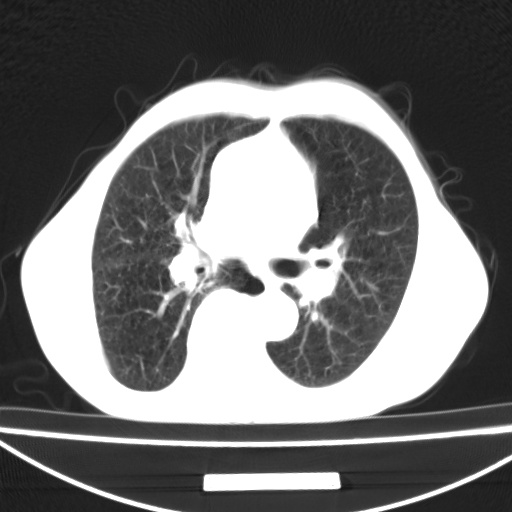

标题: CT13796:请会诊右上费病变!

患者男80岁,反复咳嗽多年,咳喘伴咯血1月

右上肺周围型肺癌伴肺门淋巴结转移.右上肺继发型肺结核.

右上肺周围型肺癌伴肺门淋巴结转移

右肺上叶占位性病变,考虑周围型肺癌,肺门淋巴结转移。要是能提供更多的临床资料就好了,以供鉴别诊断。

右肺尖周围型肺癌伴肺门淋巴结肿大

右肺上叶占位性病变,考虑周围型肺癌,肺门淋巴结转移。

考虑为:右肺上叶肺癌伴阻塞性肺炎、右肺门及纵膈淋巴结转移。